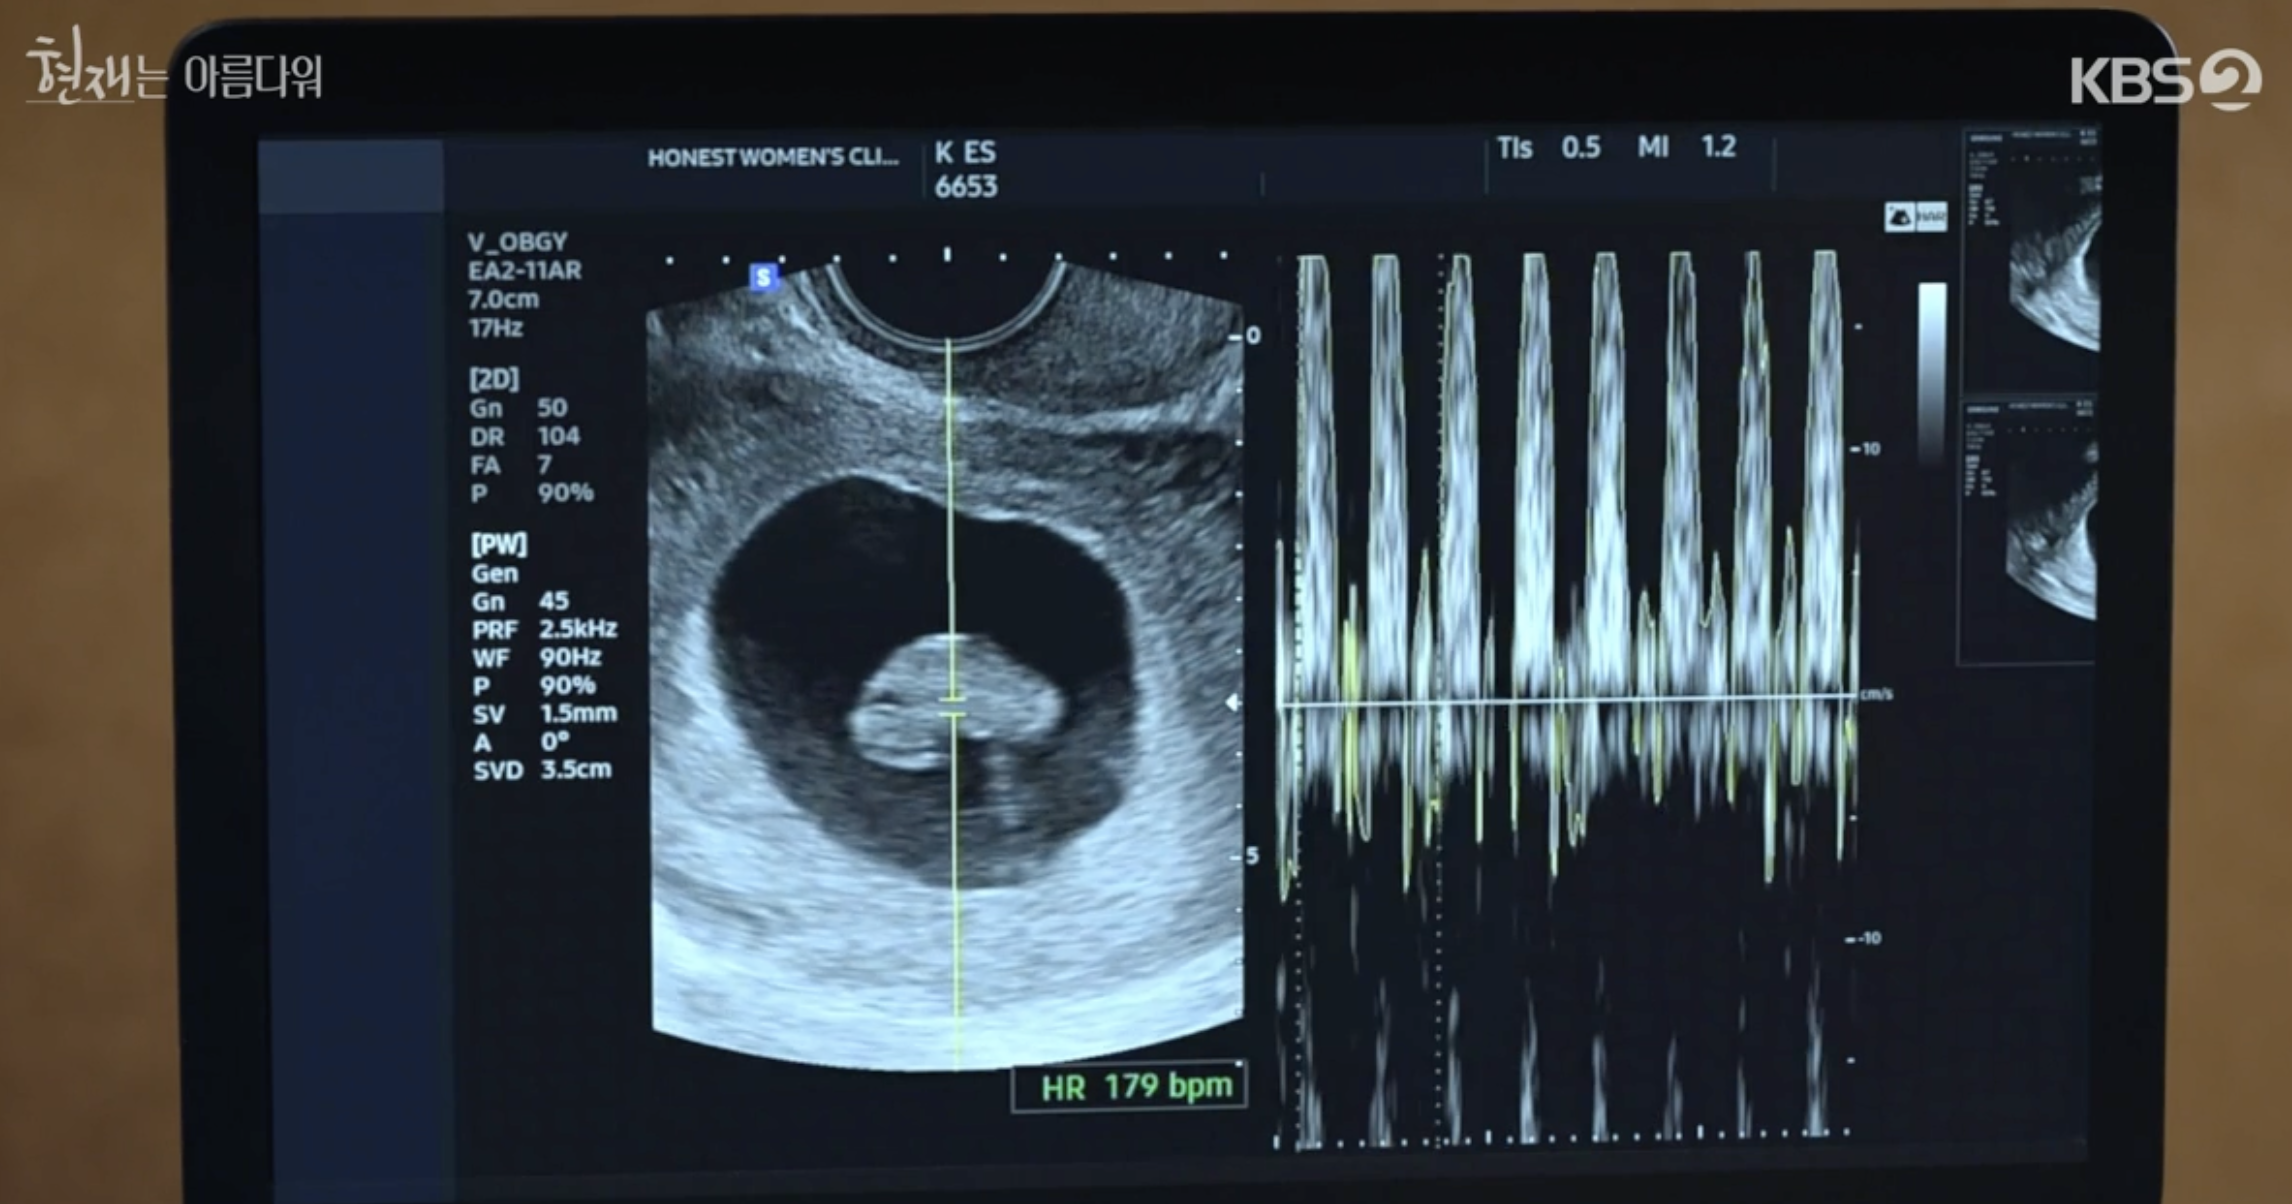

미래의 산부인과 검진

산부인과 검진이 양호하자 현재와 미래는 기뻐한다. 산부인과 검진 후 미래는 현재에게 이식 수술에 대한 불안한 마음을 전한다. 이에 현재는 어머니와 나 둘 다 사는 길을 결정했다고 말한다.